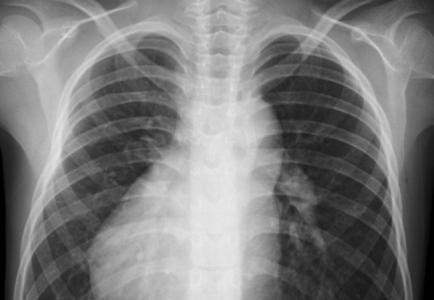

ACHALASIE : L’IA et les radios pour un diagnostic non invasif

L’intelligence artificielle (IA) appliquée aux radiographies pourrait grandement faciliter le diagnostic complexe de l’achalasie, conclut cette équipe de l’Université métropolitaine d'Osaka. L’équipe décrit dans la revue Clinical Gastroenterology and Hepatology, comment l’IA peut « repérer » la dilatation typique observée au niveau de l’œsophage dans des affections comme l'achalasie.